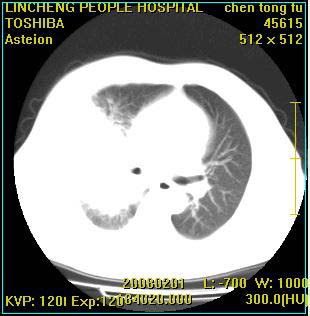

患者,男性,62岁。主因头晕,发热,咳嗽6天,高热达39度,esr19mm/h,wbc 3.9×10 9/l

大叶性肺炎并胸膜炎

右肺大叶性肺炎,胸腔积液。建议痰检。

实变区见空气支气管征,支气管通畅,考虑为大叶性肺炎,右侧少量胸水

1)考虑为:右肺感染性病变。建议:抗炎治疗复查。2)右侧少量胸腔积液。

考虑为右肺大叶性肺炎,胸腔积液,建议必要时纤维支气管镜检查,以排除肿瘤性病变。

右肺炎症并右侧胸腔少量积液。

考虑为右肺大叶性肺炎伴少量胸腔积液,建议复查,如病变不吸收或吸收不明显,建议纤维支气管镜检查,除外细支气管肺泡癌的可能。

右侧大叶性肺炎,右侧少量胸腔积液.

实变区见空气支气管征,支气管通畅,考虑为大叶性肺炎,右侧少量胸水。